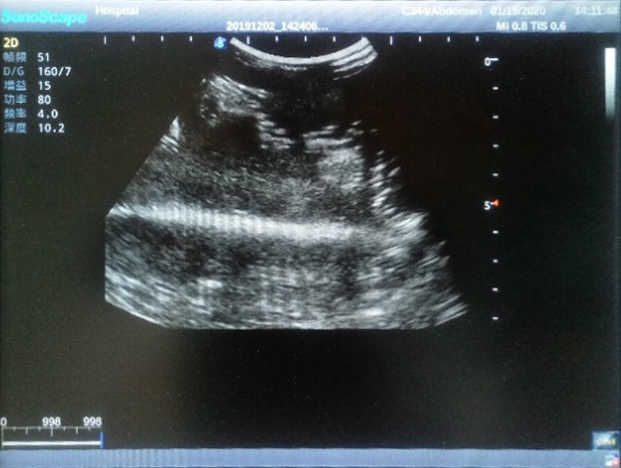

Outline

4) Biomimetic material allowing users to see clear and real normal tissues and space-occupying lesions that are hyperechoic, hypoechoic and isoechoic as they would see in the clinical environment